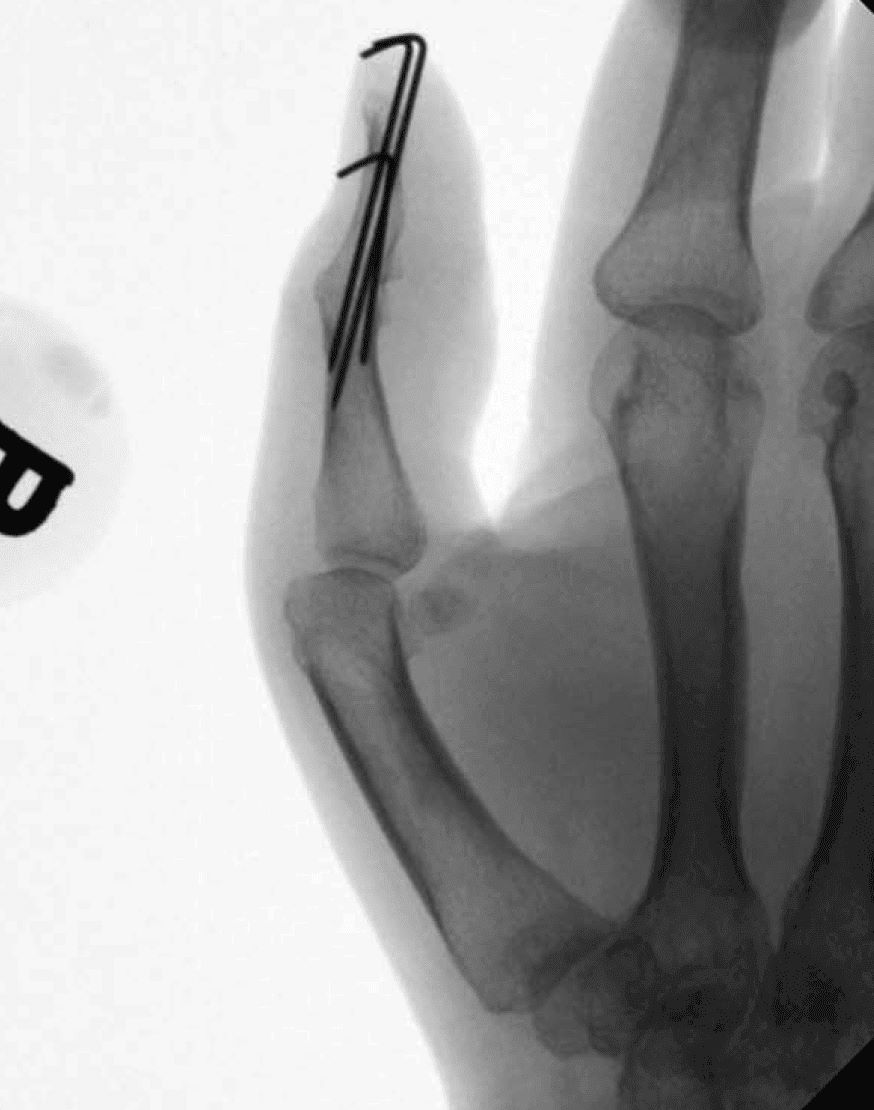

X-ray Showing Thumb Fusion

Thumb following interphalangeal joint arthrodesis (fusion) with pins. These pins will be removed after the fusion is completed, because they stick out of the skin.

Reproduced from Beldner S, Polatsch DB. Arthrodesis of the Metacarpophalangeal and Interphalangeal Joints of the Hand: Current Concepts. J Am Acad Orthop Surg. 2016;24(5):290-297. doi:10.5435/JAAOS-D-15-00033